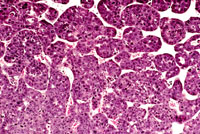

Higher magnification of liver lesions in a 4-week old AL-TAg x AL-myc mouse.

Higher magnification of a well differentiated cholangiocarcinoma in a 4-week old AL-TAg x AL-myc mouse.